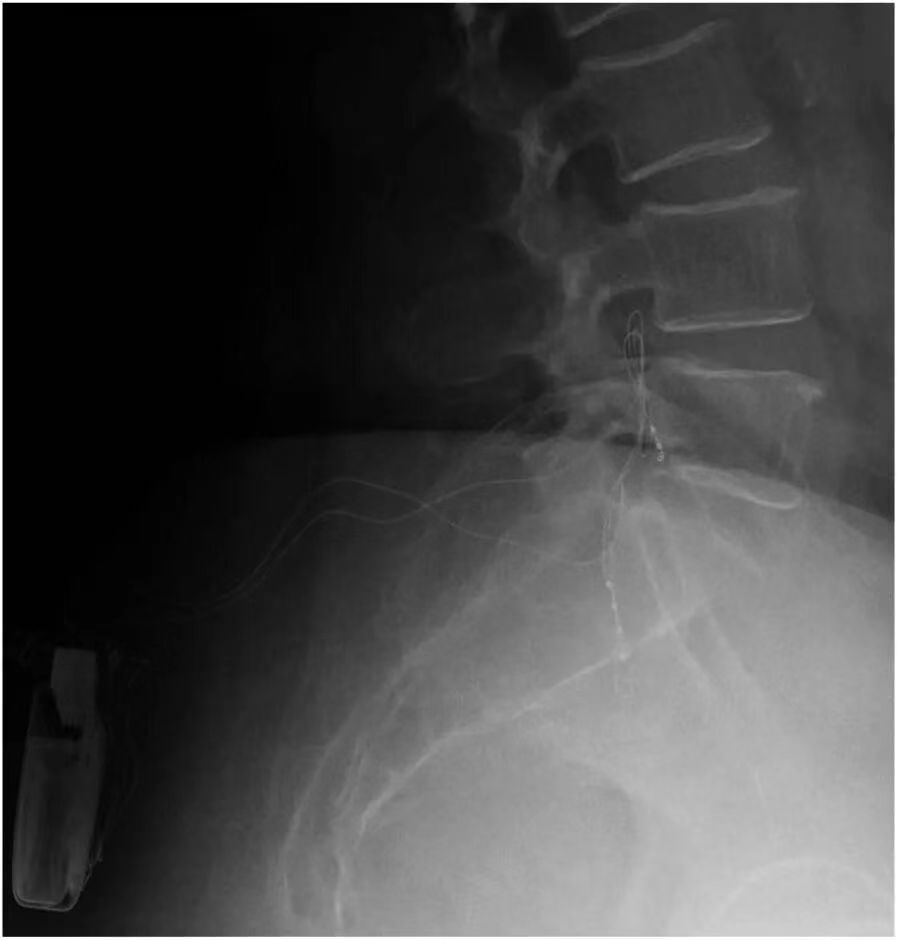

如果患者在试验期内对脊髓电刺激反应良好,且医生认为长期治疗可能对患者有益,那么就会考虑进行永久植入手术。在手术前,医生会与患者充分沟通,讨论植入的具体方式、预期的治疗效果以及可能存在的风险等。手术过程中,患者通常会接受全身麻醉或局部麻醉,医生会在透视引导下,将永久性电极精准地植入到硬膜外间隙,并确保电极与脊髓的位置关系合适。电极植入后,会将其与植入式脉冲发生器(IPG)相连,IPG 通常会被放置在患者的腹部或臀部皮下。手术后,医生会对 IPG 进行编程,根据患者的个体情况设置合适的刺激参数,以达到最佳的治疗效果。